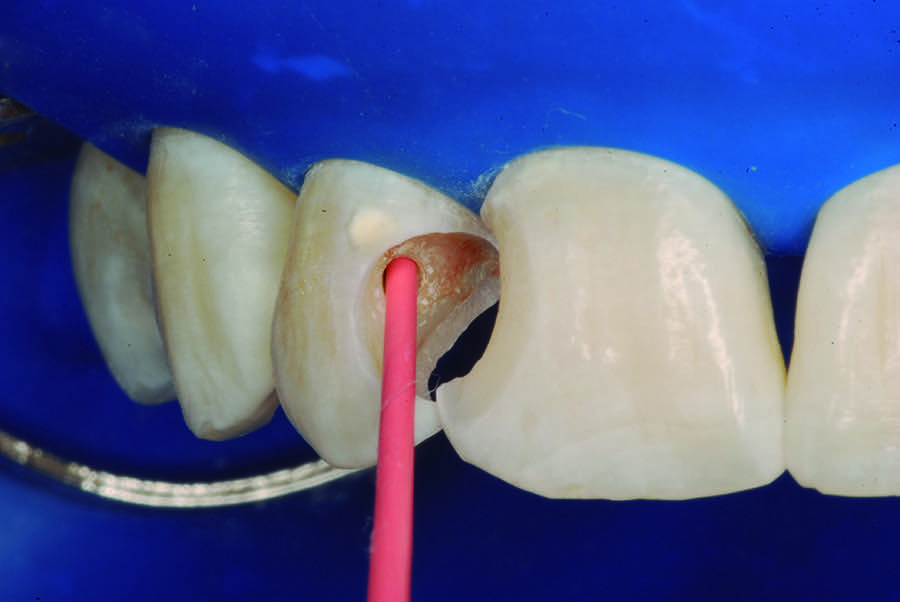

The partial pulpotomy was performed for tooth No. 7 due to the pulp exposure during the caries removal procedures (Figure 5). The superficial contaminated pulp tissue was removed with a No. 1012 spherical diamond bur at high speed with water cooling to allow a better reparative response. This procedure was limited to removal of the infected dentin and damaged pulp tissue, removing the injured odontoblast cell layer. During this step, the remaining pulp tissue was analyzed and found to have good consistency and abundant red bleeding (Figure 6). After the pulpotomy, a solution of calcium hydroxide was used for irrigation along with a sterile cotton pellet to achieve hemostasis and disinfection. After hemostasis, the tooth was treated with direct pulp capping: the exposed area was covered with calcium hydroxide powder (Figure 7) and calcium hydroxide cement (Figure 8). The cavity was provisionally restored with the use of a restorative GIC (Figure 9).

Fig 5. Partial pulpotomy with No. 1012 diamond bur under water cooling.

Figure 5